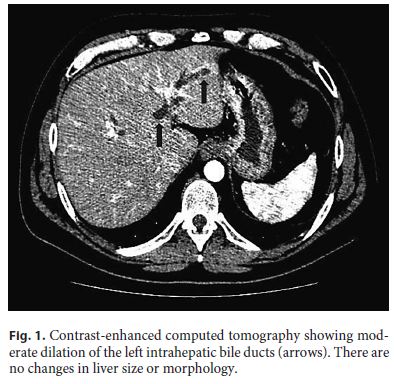

The patient underwent an abdominal ultrasound followed by contrast-enhanced computed tomography (Fig. 1), which together showed dilated left intrahepatic ducts and common bile duct, reaching 7 mm, with no obstructive lesion; no gallstones were detected. Magnetic resonance cholangiopancreatography (MRCP) identified a 4-mm stone in the proximal common bile duct, with upstream dilation (Fig. 2). Due to a progressive rise in CRP (5.4 mg/dL), the patient was put on ciprofloxacin assuming cholangitis. An endoscopic retrograde cholangiopancreatography (ERCP) was then performed, with sphincterotomy, extraction of the common bile duct stone with a basket and multiple other smaller stones, which were yellow in color. Considering the high risk of stone migration, a plastic biliary stent was placed to prevent complications prior to cholecystectomy.